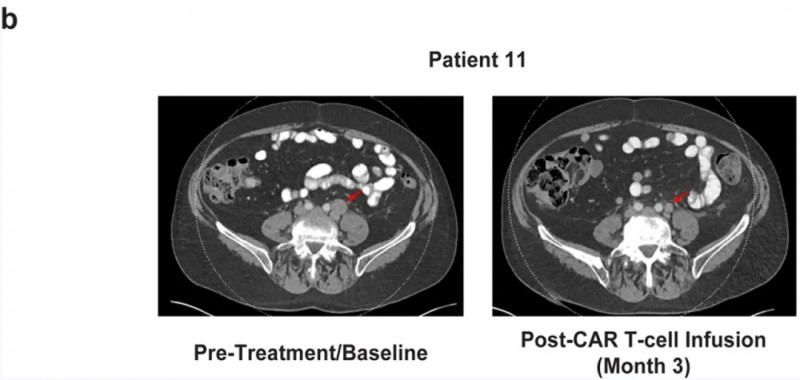

值得注意的是,计算机断层扫描显示11号患者,在接受自体CART-PSMA-TGFβRDN治疗后,出现肿瘤消退,血清PSA水平下降36%。其治疗前及CAR-T细胞过继转移后3个月的放射学检查结果详见下图,肿瘤部位以红色箭头标出。

▲图源“Nat Med”,版权归原作者所有,如无意中侵犯了知识产权,请联系我们删除